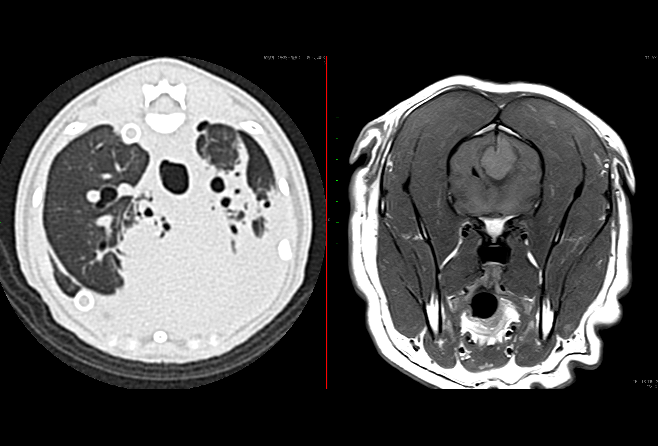

研究内容

主に画像診断とその先の治療に関連する研究を行っています.レントゲン(X線)、超音波、コンピューター断層撮影(CT)、磁気共鳴画像(MRI)、内視鏡などを用いて,様々な癌(腫瘍班)や呼吸器疾患(呼吸器班)あるいは脳神経疾患(神経班)について基礎的・臨床的に研究しています.

• レントゲン,エコー(呼吸器)、内視鏡(呼吸器)、CT,MRIの基本的な知識と読影技術

• 腫瘍班:様々な腫瘍の診断や治療についての知識

• 呼吸器班:鼻、咽頭、喉、気管,肺といった呼吸器の病気に関する基礎知識と診断,治療に関する知識

• 神経班:脳神経疾患の知識と診断,治療法に関する知識